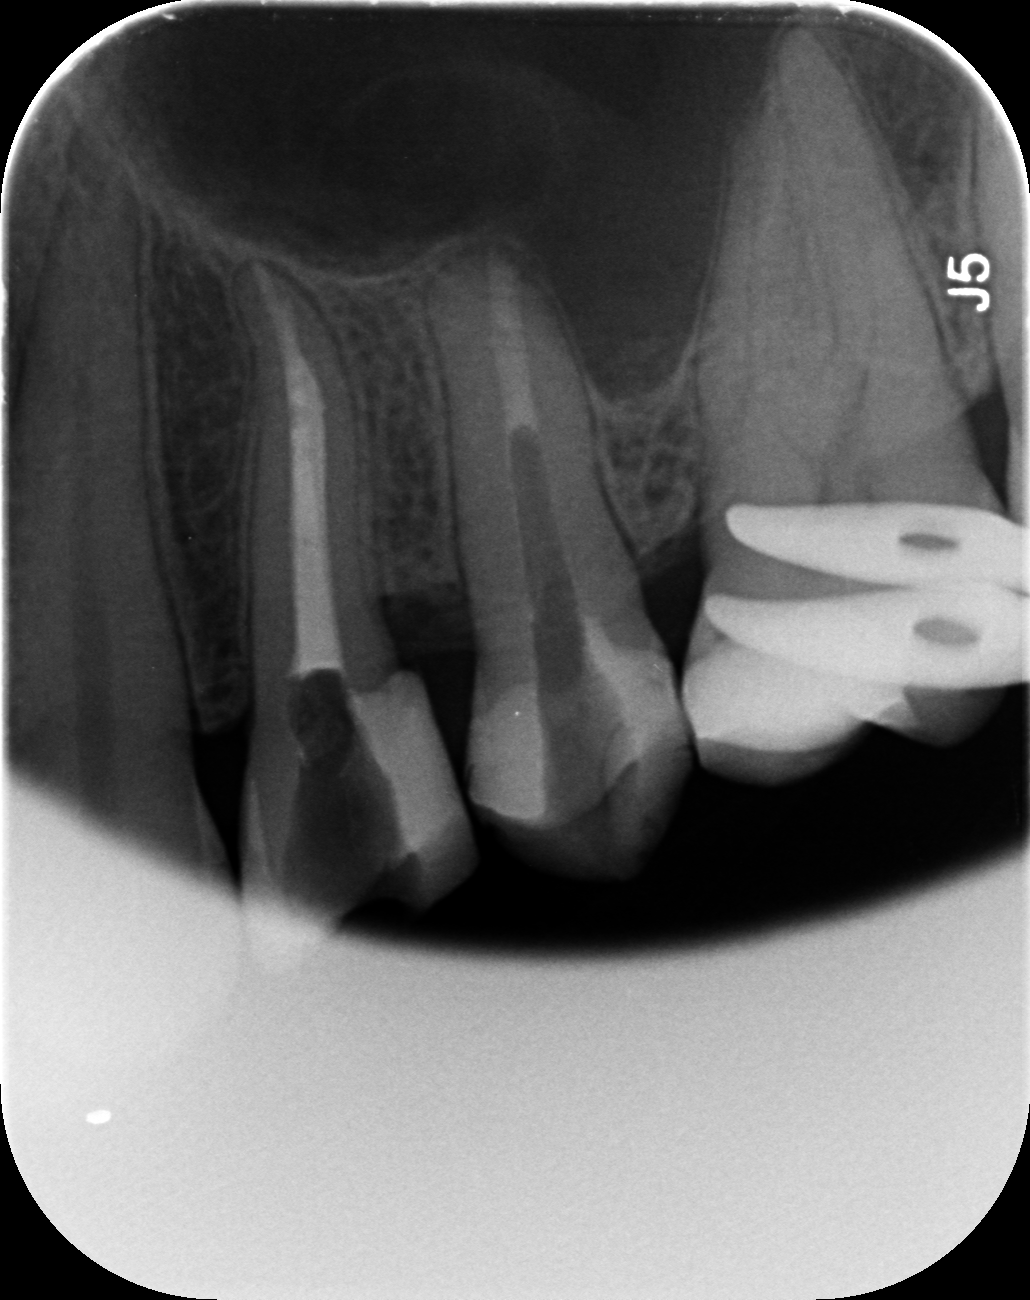

Dantų kanalų gydymas